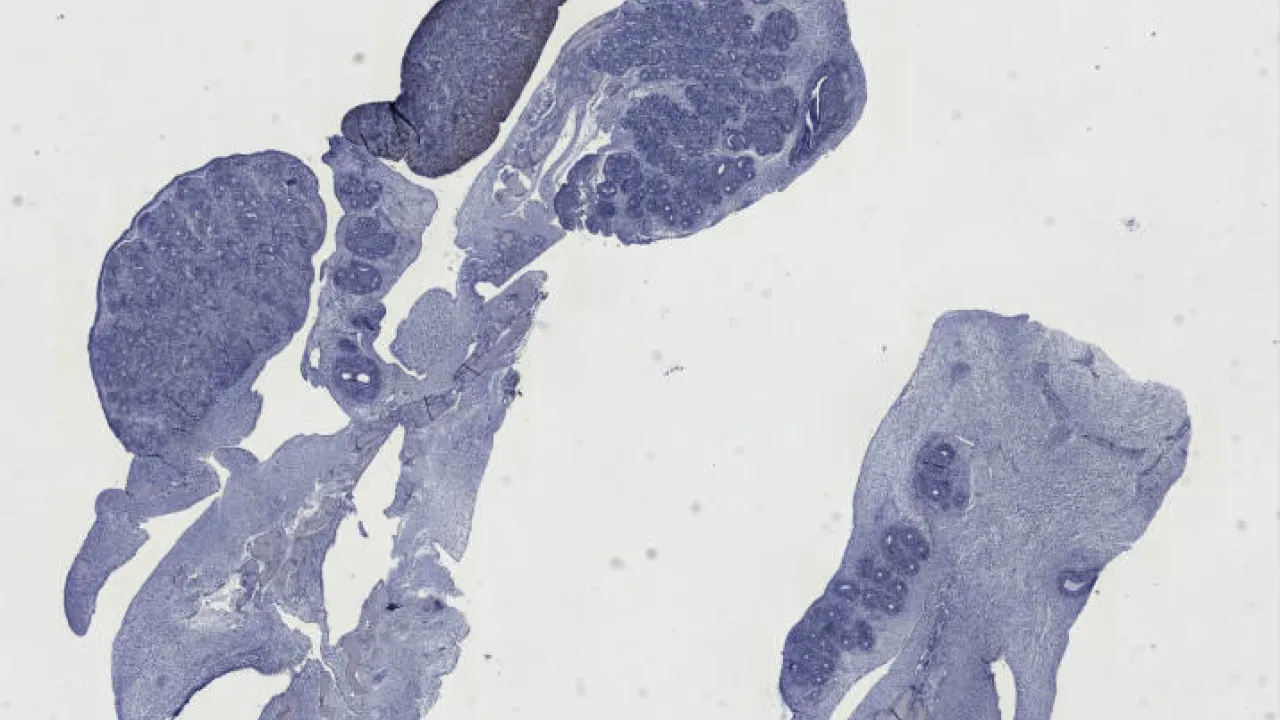

Lower Urinary Tract and Male Genital System